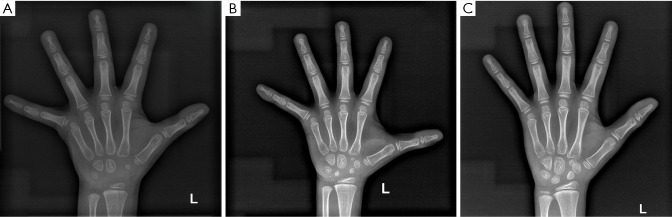

Case description: In this report, a female child is described who exhibited slow weight and height gain since birth. At 18 months, physical examination revealed that her height was below the 3rd percentile, with bone age delayed by 3 months. No typical NS facial features or congenital heart defects were observed. GH stimulation testing indicated partial GH deficiency, and the insulin-like growth factor 1 (IGF-1) level was below normal; thus, a preliminary diagnosis of short stature due to GH insufficiency was made, and nutritional intervention was recommended. However, follow-up revealed a persistent slow growth velocity and progressive bone age delay. At 6 years and 1 month of age, whole-exome sequencing identified a heterozygous c.923A>G (p.Asn308Ser) variant in the PTPN11 gene, confirming the diagnosis of NS. Recombinant human growth hormone (rhGH) therapy was subsequently initiated. After rhGH intervention, the patient's annual height velocity increased by 2.4 to 3.2 times compared to pretreatment, which was accompanied by synchronous progression of bone age.